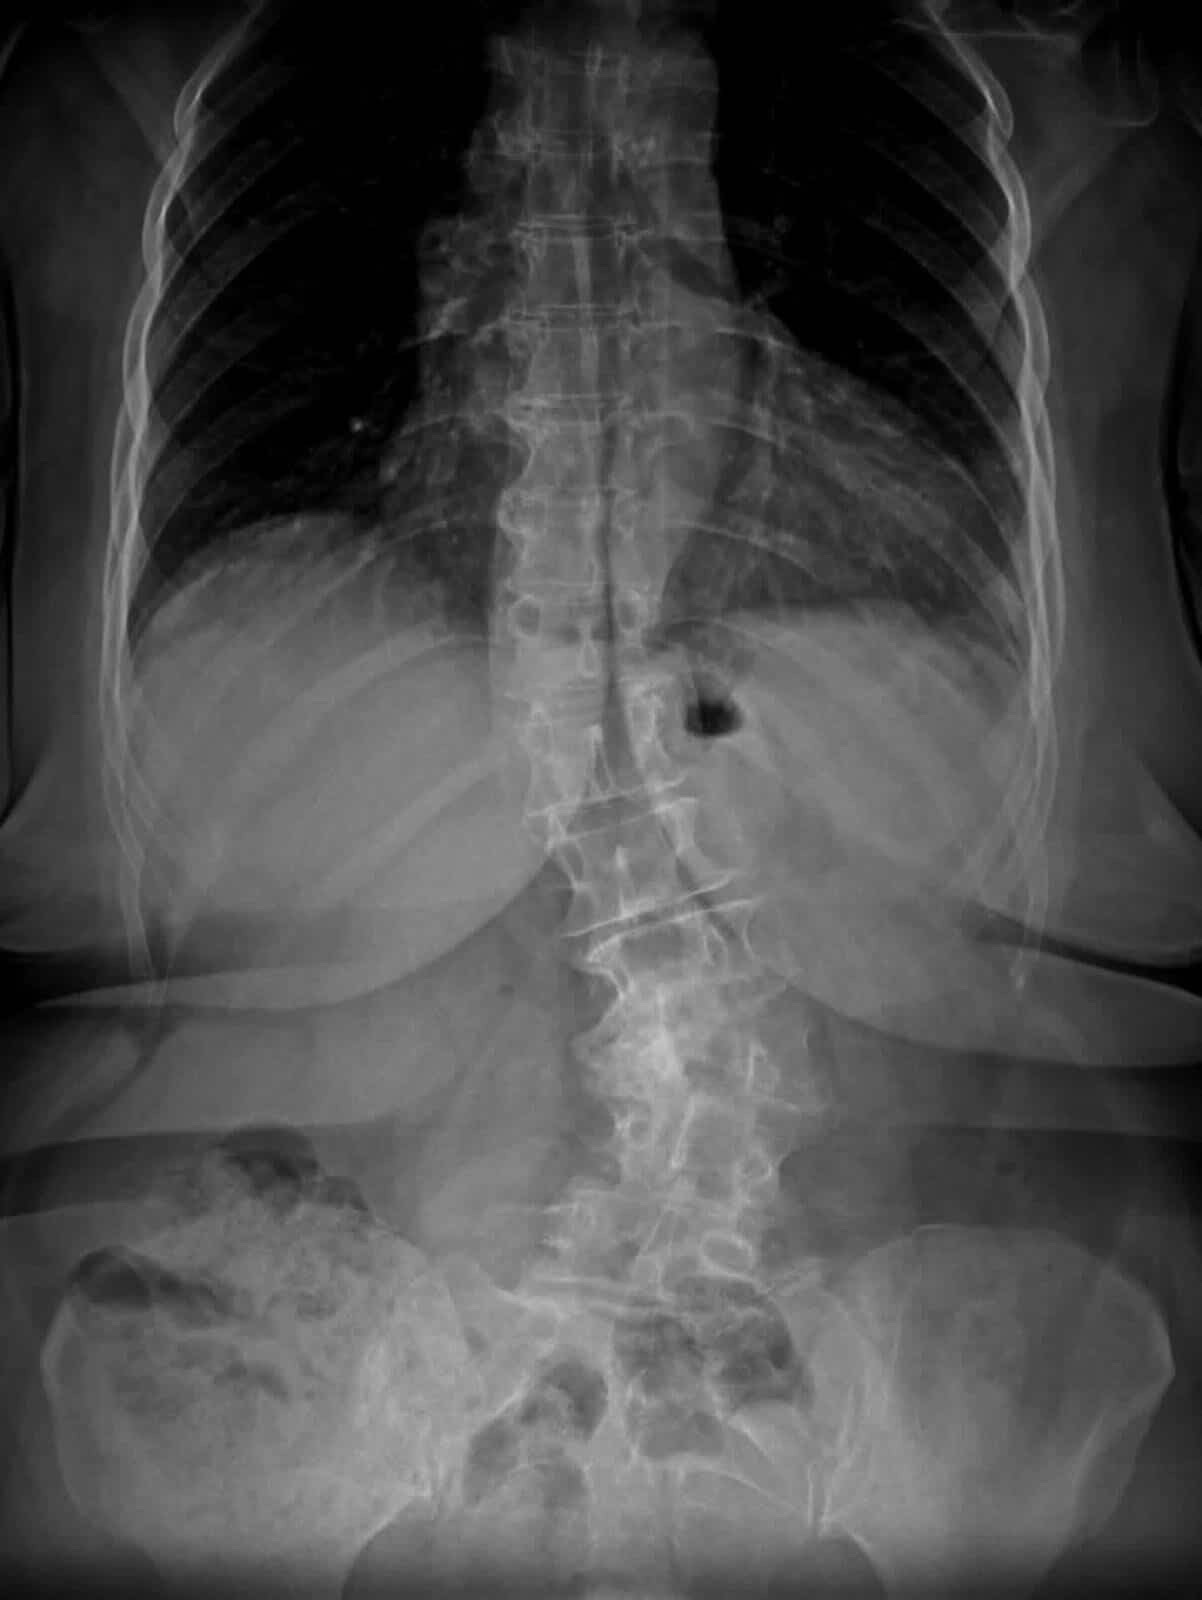

Yapılan tetkik ve değerlendirmeler sonucunda hastaya dejeneratif skolyoz tanısı konulduğunu ifade eden Topal, şu bilgileri paylaştı:“Polikliniğimize bel ve bacak ağrısı, duruş bozukluğu ve yürüme güçlüğü şikâyetleri ile başvuran hastamıza yapılan değerlendirmeler sonucunda dejeneratif skolyoz tanısı konuldu ve cerrahi tedavi planlandı. Ameliyat sırasında omurgada sinirlere baskı oluşturan, kanal daralmasına neden olan disk bozuklukları, kemik dejenerasyonları ve kireçlenmiş yumuşak dokulara müdahale edildi.”

Ameliyat sırasında hastanın omurgasında yaklaşık 30 derece olan eğriliğin 6 dereceye kadar düzeltildiğini belirten Topal, operasyonun ardından hastanın ertesi gün ayağa kaldırıldığını söyledi. Başarılı operasyon sonrası hastanın bel ve bacak ağrılarının belirgin şekilde azaldığı, duruş ve yürüme bozukluğunun düzeldiği ifade edildi. Hasta, yapılan takiplerin ardından taburcu edildi.